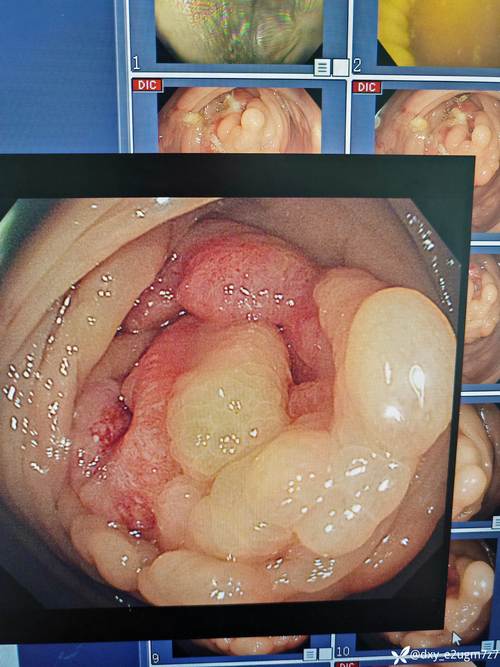

行结肠镜检查提示距肛门约15cm有一菜花样肿物,侵及肠腔近半周,活检